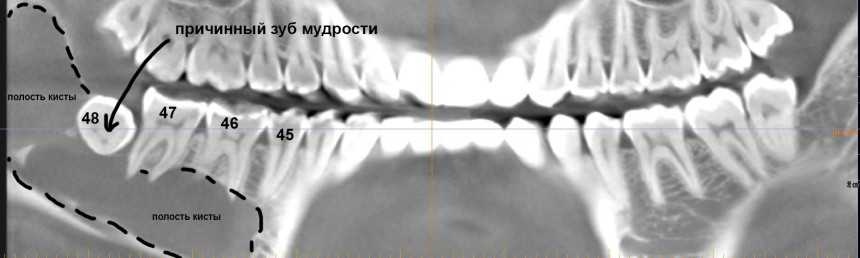

Но самое неприятное, что можно ждать от ретинированных зубов мудрости – это кисты.

Их источником является фолликул, окружающих зачаток зуба. Когда зуб прорезывается, фолликул исчезает, но в случае ретенции он сохраняется и может служить источником опухолей и кист. Иногда – достаточно больших и весьма опасных для здоровья.